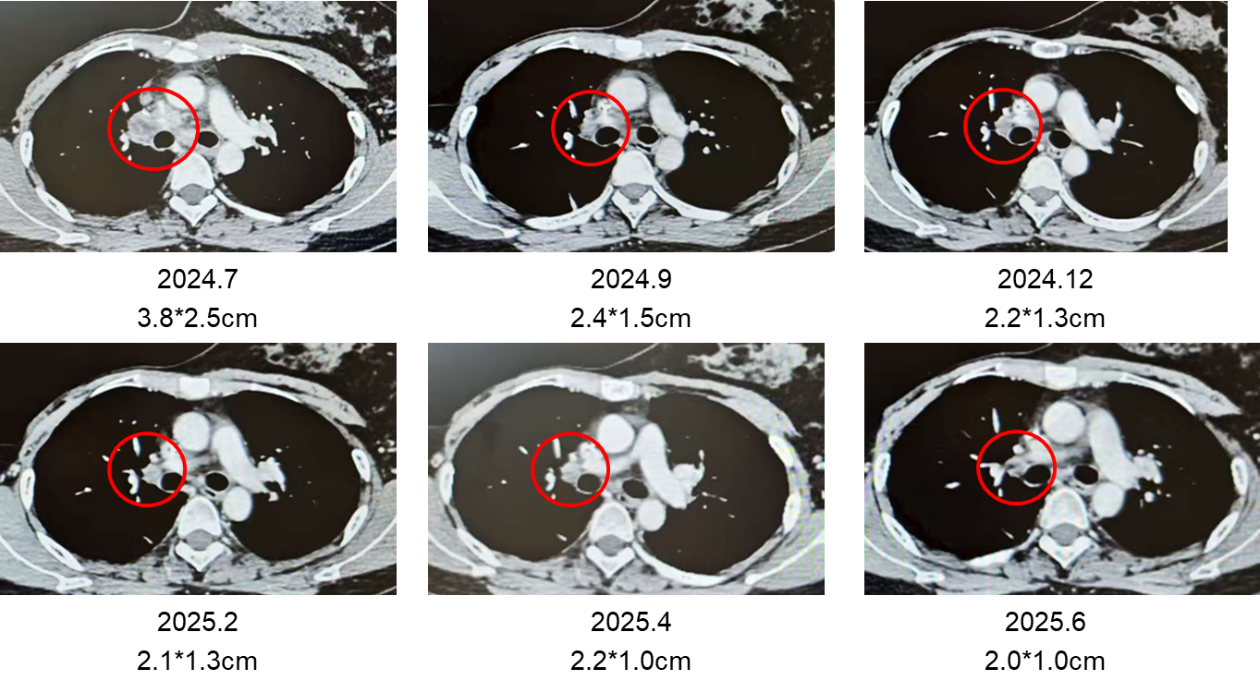

图1 2024 年 7 月至 2025 年 6 月期间定期复查CT显示,靶病灶(肺门淋巴结)大小持续缩小

2024年7月,患者经EBUS穿刺活检证实肺门淋巴结转移,免疫组化仍为HER2(3+)。患者2024.6.25入组一项瑞康曲妥珠单抗(SHR-A1811)的III期临床研究(注射用SHR-A1811±帕妥珠单抗对比THP治疗HER2阳性复发或转移性乳腺癌的多中心、随机、开放、阳性对照III期临床研究;方案编号SHR-A1811-307),2024.7.29随机至SHR-A1811单药组(4.8mg/kg),并持续治疗至今。疗效评估为部分缓解(PR)。

本例患者为HER2阳性、腋窝淋巴结阳性乳腺癌患者,早期接受AC-THP方案辅助治疗,符合《中国临床肿瘤学会(CSCO)乳腺癌诊疗指南》的推荐标准。随访3年余,患者出现肺门淋巴结转移,随即入组SHR-A1811-307临床试验。值得关注的是,新型抗HER2 ADC瑞康曲妥珠单抗作为一线治疗方案展现出显著疗效,靶病灶持续缩小,达到PR标准。与此同时,患者也出现了ADC药物相关的中性粒细胞减少事件。